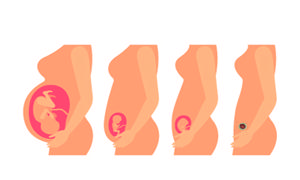

对于处于备孕期间的男女双方来说,都会多加注重生活和饮食等各方面的调养,以便提高受孕几率,而想要受孕成功,把握好时机也是必不可少的,那么,什么时候容易受孕?

从怀孕开始,女性的身体就悄悄出现变化,孕期的各种不适也接踵而至。而从怀上宝宝到生出宝宝,整个孕期里孕妈都需要特殊照顾。特别是孕早期,这是孕妈和家人们最紧张也最容易产生不适的阶段。如何安然度过孕早期?怀孕早期注意事项有哪些呢?

怀孕早期绝对是每个准妈妈最激动和最不适的时段,在这期间从心理上的转变到身体上的转变都会给你带来很多心理压力,而且孕早期的早孕反应会让你食不知味、夜不能眠,也许你的脾气、习性也在潜移默化中变得喜怒无常,让你老公有点措手不及,其实不用过于担心,只要你确保饮食、适量运动,都不会有太大问题,下面就跟妈网小编一起来了解下孕早期症状吧,提早做好心理准备,到时候就不会手忙脚乱的了。